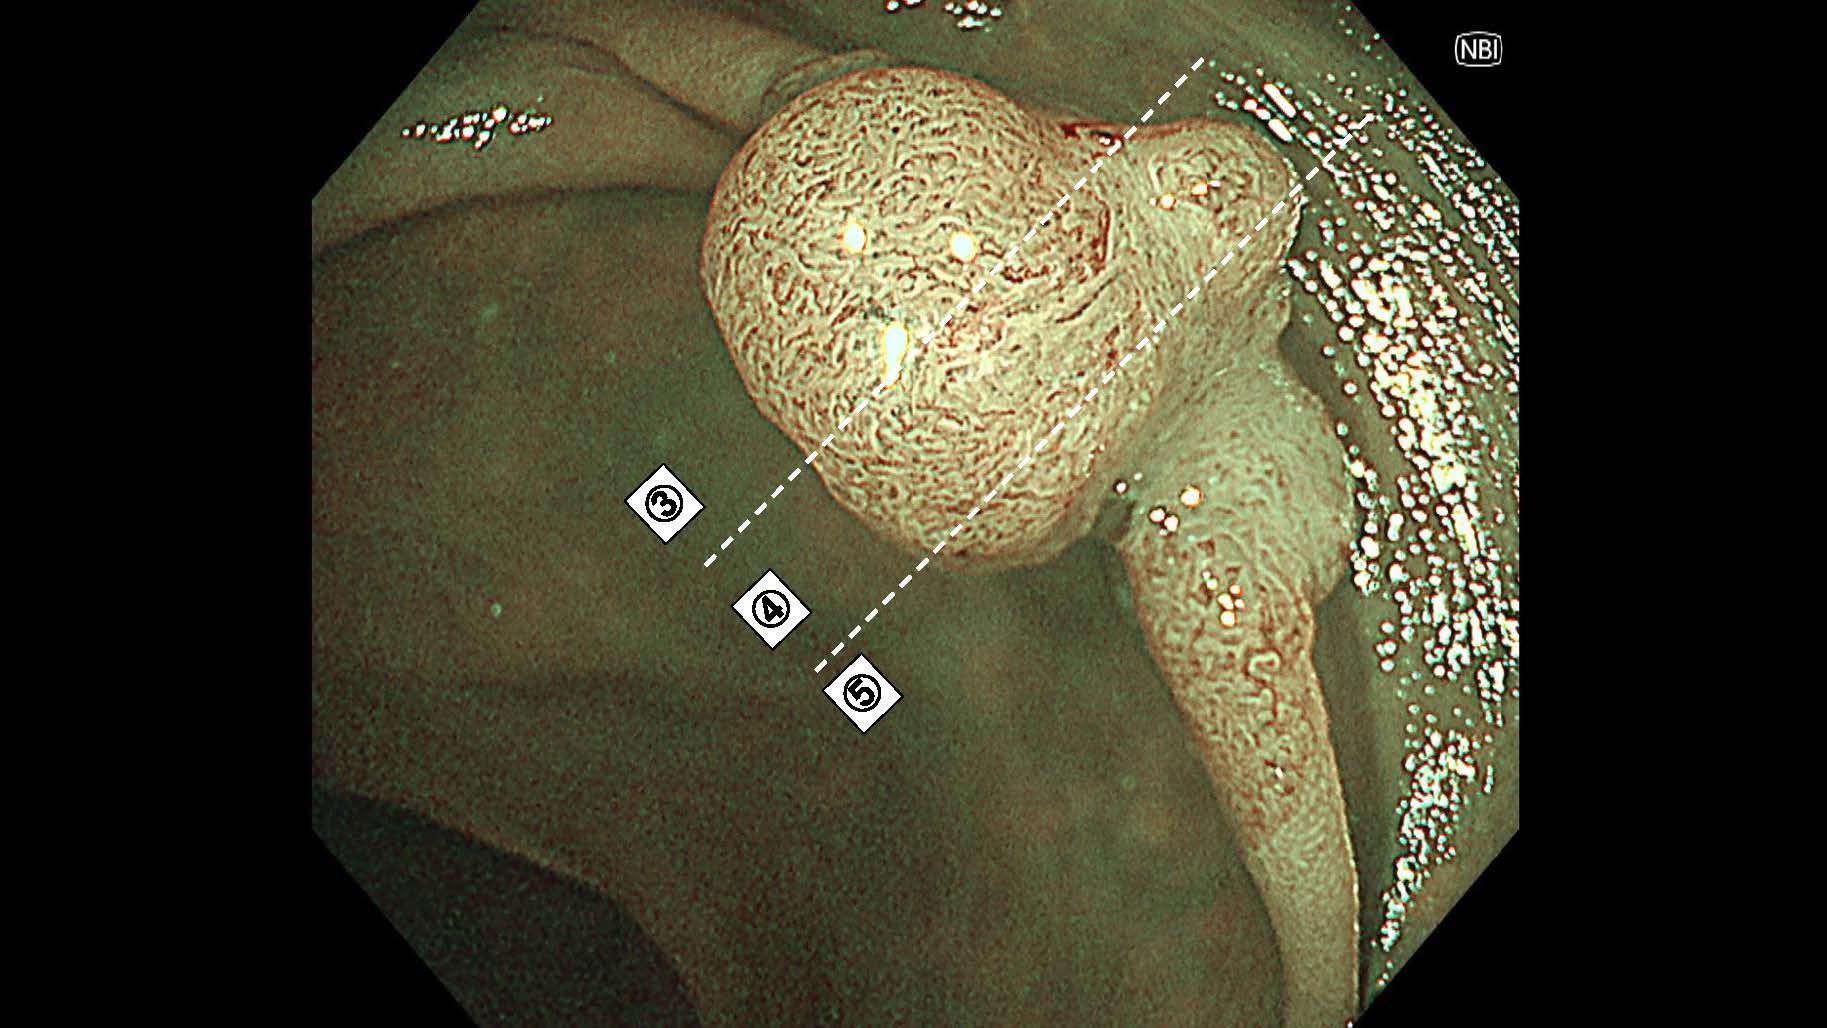

消化管Mapping~大腸~ 2025.6.11

消化管Mapping

消化管Mapping~大腸~

消化器内科

内視鏡検査・治療